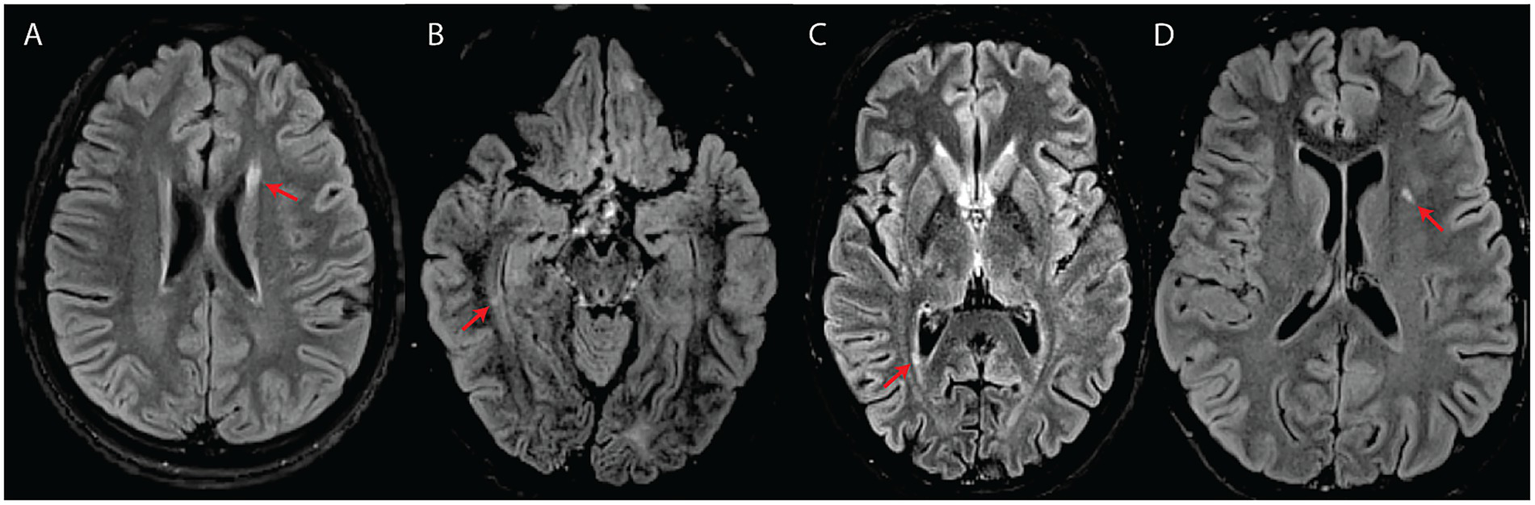

We detected T2-hyperintense white matter foci that were MS plaque-like (27–29) in seven subjects (n = 7/17; 41%) (Figures 2, 3). In four of these subjects (n = 4/17; 24%), the McDonald radiological criteria of dissemination in space and time were either fully (n = 3) or partially (n = 1) fulfilled, inciting consideration of a WFS-MS double diagnosis (Figure 2) (27). Some lesions in three of these four subjects showed gadolinium enhancement on T1-weighted imaging (Figure 2A), further supporting the existence of an underlying inflammatory process. Positive oligoclonal band status strongly supported a secondary diagnosis of MS (satisfaction of the full McDonald criteria, radiological and clinical) in the only two subjects for whom lumbar puncture was performed (#2 and #3). In both cases, a secondary diagnosis of MS was therefore communicated due to the presence of accompanying acute focal clinical deficits. MS treatment with teriflunomide was initiated in subject #3. Follow-up MRI after teriflunomide initiation documented stabilization of the multifocal white matter lesion load with worsening of pre-existing cerebellar atrophy and diffuse bilateral subcortical white matter involvement (Figures 2G–I). The observed locations and characteristics of MS-like focal lesions are summarized in Table 2.

Figure 3

White matter abnormalities suggestive of an inflammatory process (A–C) or classified as intermediate (D) in four subjects with WFS. All images are axial T2-FLAIR. (A) Elongated lesion located at the level of the anterior horn of the left lateral ventricle (subject #7). (B) Small temporal periventricular lesion perpendicular to the right ventricular wall (subject #7). (C) Small periventricular lesion perpendicular to the right ventricular wall (subject #10). (D) Left insular deep white matter lesion classified as intermediate between suspicious for inflammatory process and typical for WFS (subject #8).

Overall, the interrater agreement was substantial, with a Cohen’s κ value of 0.729 (standard error = 0.087; 95% confidence interval = 0.559 to 0.899). Specifically, during blind re-analysis 4 months after the first image review, it was agreed that three subjects (#7, #8, and #13) had focal lesions not strictly belonging to either category (WFS- or MS-like/demyelinating) (Figure 3D; see Table 1 for initial lesion categorization in each subject). The areas of suspicion were in the subcortical white matter and included two or more small, round, yet non-ovoid T2-hyperintense lesions close to one another. The lesions did not correspond to enlarged perivascular spaces.